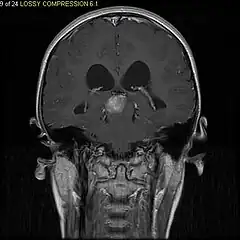

Stereotactic MRI brain scan showing a recurrent postoperative brain stem cystic pilocytic astrocytoma. -

Pilocytic astrocytoma in the hypothalamic region. -

Sagittal T1-weighted MRI showing a well-circumscribed hypointense mass in the tectum (presumably a tectal plate glioma). These lesions are a distinct subset of pilocytic astrocytoma which present with hydrocephalus typically in 6 to 10 year-olds and are rarely progressive lesions. When imaging is characteristic, a biopsy is usually not performed because of the risks to adjacent structures, often shunting to relieve intracranial pressure is the only treatment required. -

T1-weighted coronal MRI image postcontrast showing heterogeneous contrast enhancement within the presumed tectal plate glioma

Usually – depending on the interview of the patient and after a clinical exam which includes a neurological exam and an ophthalmological exam – a CT scan and/or an MRI scan will be performed to confirm the presence of a tumor. They are usually easily distinguishable from normal brain structures using these imaging techniques. A special dye may be injected into a vein before these scans to provide contrast and make tumors easier to identify. Pilocytic astrocytomas are typically clearly visible on such scans, but it is often difficult to say based on imaging alone what type of tumor is present.